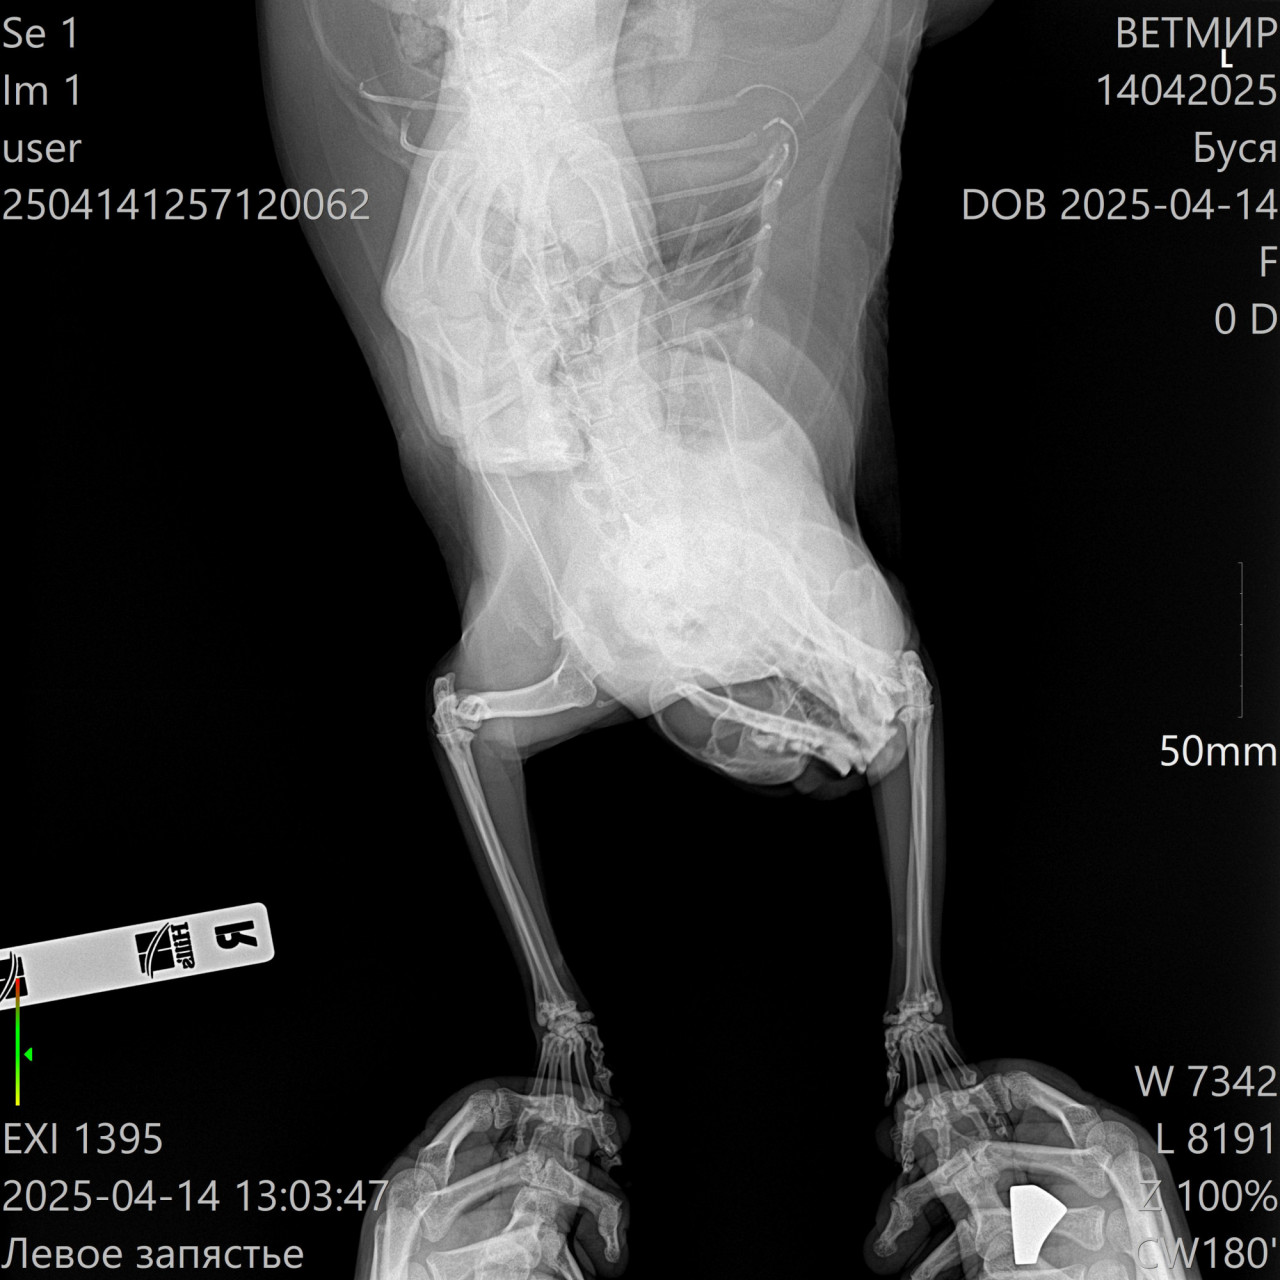

Здравствуйте. По рентгеновским снимкам у кота визуализируются дегенеративные изменения в области задних конечностей и возможные признаки остеоартроза или дисплазии тазобедренных суставов. Также может быть травматическое повреждение или врождённая деформация. Хромота в таком возрасте (12 лет) часто связана с возрастными изменениями в суставах. Необходима консультация ветеринарного ортопеда, возможно  курс противовоспалительной терапии, хондропротекторы и контроль массы тела.

Здравствуйте. На снимках отмечается нарушение конфигурации суставов и вероятные признаки хронического воспалительного процесса. Возможна артропатия или последствия перенесённой травмы. Рекомендую сдать биохимию крови (в том числе СРБ, кальций, фосфор), провести УЗИ мягких тканей конечностей и обсудить с врачом возможность обезболивания и поддерживающей терапии. В тяжёлых случаях может потребоваться МРТ и даже хирургическое вмешательство.